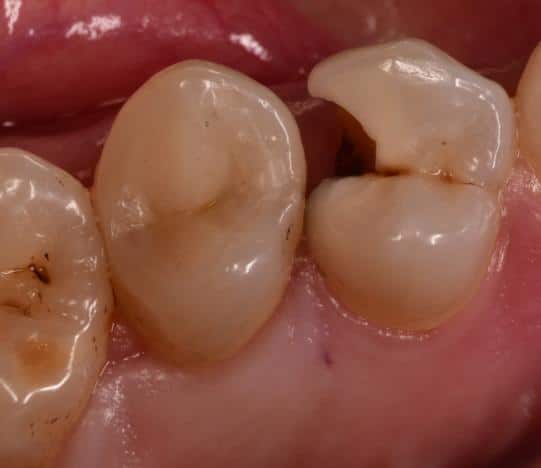

Upper 2nd premolar with deep caries lesion restored by direct composite restoration that reinforced by Ever X posterior for dentin replacement that will add more strength to the filling

Initial deep marging Cl ll cavity

14 months follow-up